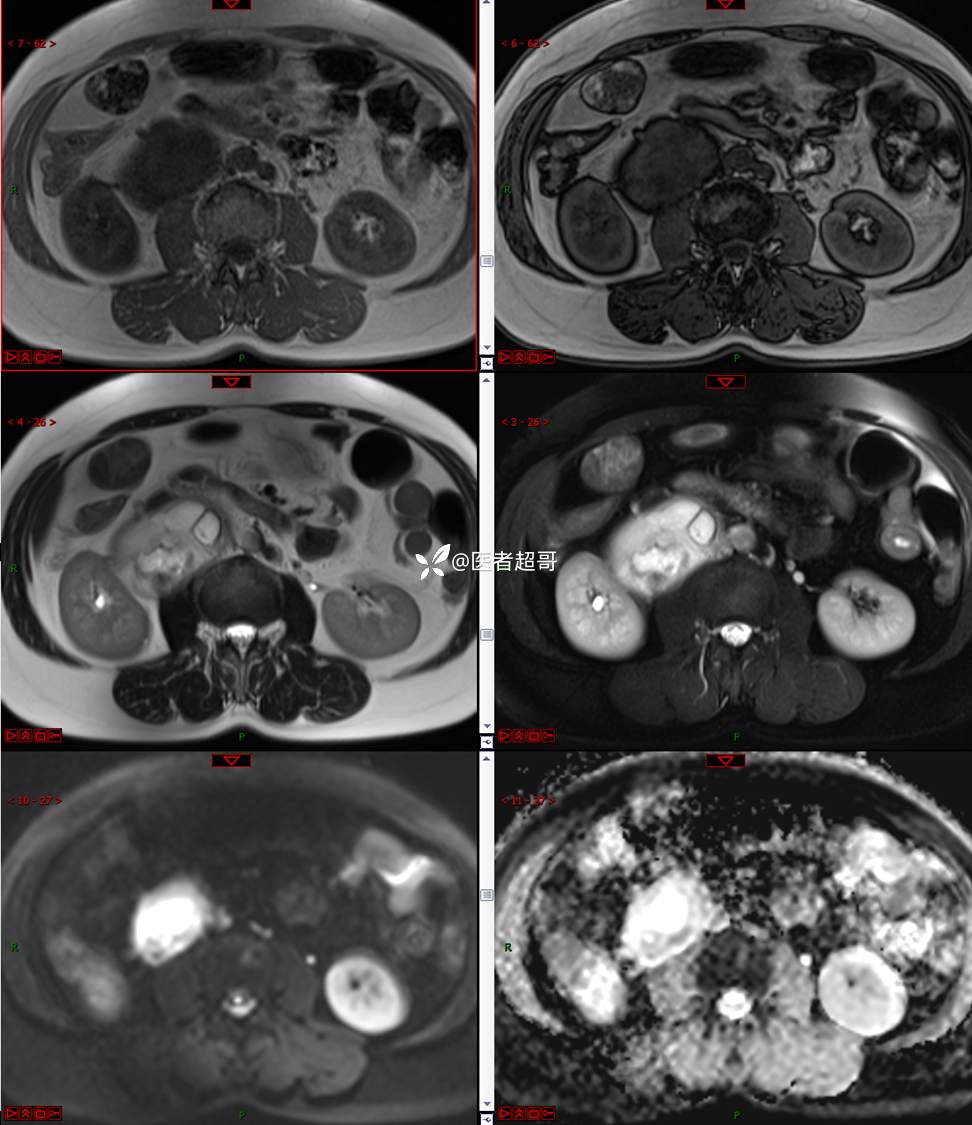

【影诊笔记671】定位有难度,究竟是腹腔内or腹膜后,请先定位,再定性!有结果~~~

专科检查:腹部平坦,腹肌软,无压痛及反跳痛,无包块,肝脾无肿大,Murphy征阴性,腹部叩鼓,肝脾双肾无叩痛,移动性浊音阴性,肠鸣音正常。我院 肝胆胰脾肾彩超提示:脂肪肝、腹腔内囊实性团块,建议进一步检查。